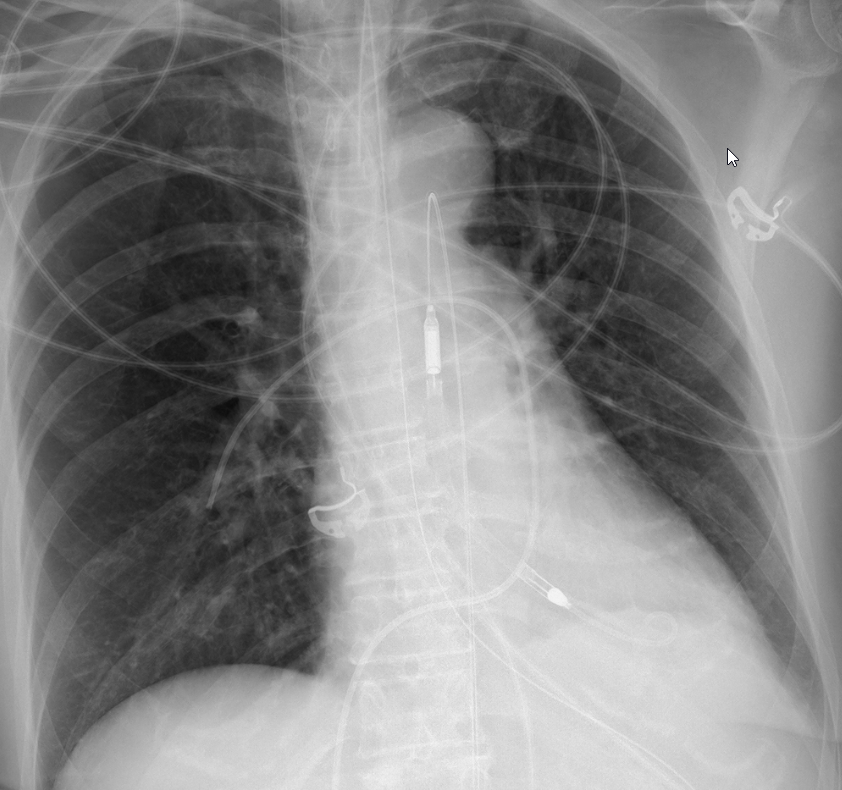

ICU (evolving) stories: A young patient was admitted with "aspiration pneumonia" a few days ago. On...

ICU (evolving) stories: A young patient was admitted with "aspiration pneumonia" a few days ago. On mechanical ventilation. Afebrile. Negative cultures. CXR when you first see him...